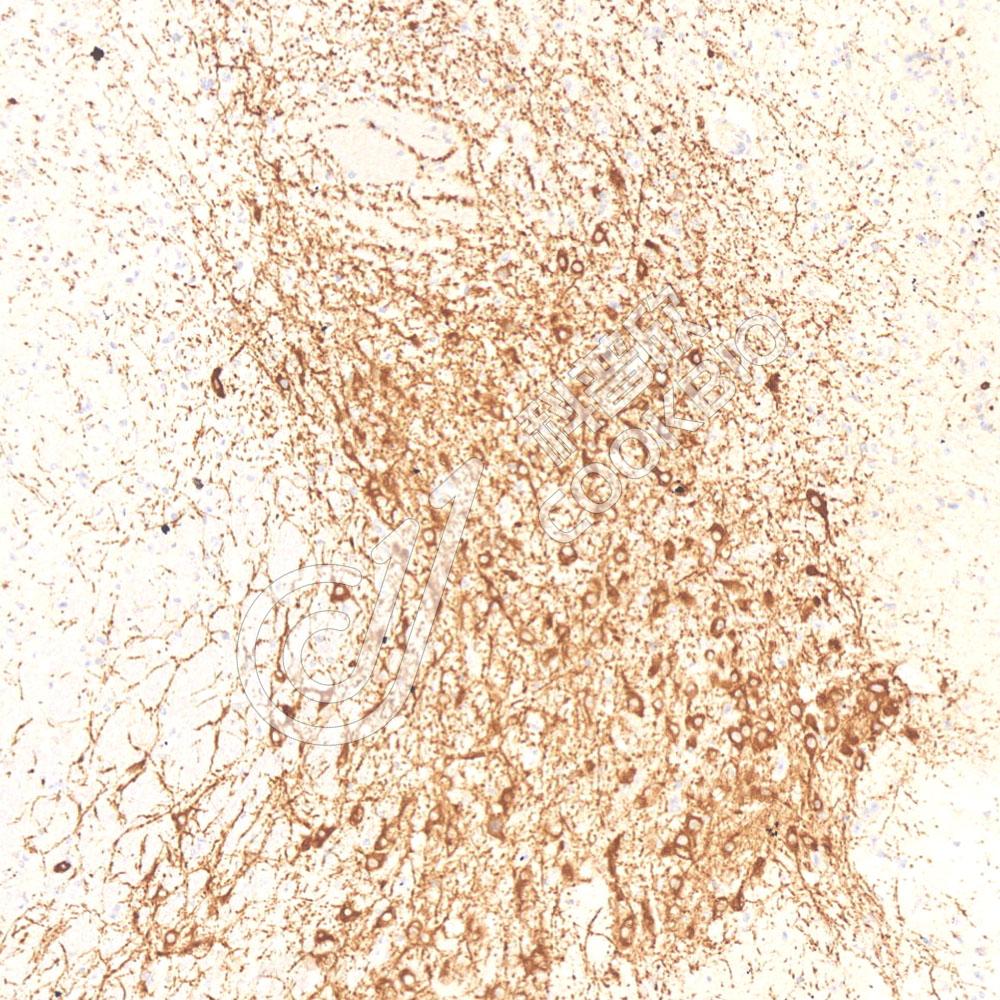

图像

WB检测Beclin 1蛋白(货号 K5467223).

样品: 经RIPA裂解液(货号KSG2002)处理的蛋白质.

封闭: 3%脱脂牛奶(货号KSGC310001)溶于TBST溶液, 室温孵育1小时.

—抗: 1: 1000稀释, 4℃ 孵育过夜.

二抗: HRP标记山羊抗兔IgG (H+L) (货号KB69909), 1: 5000稀释, 室温孵育1小时.